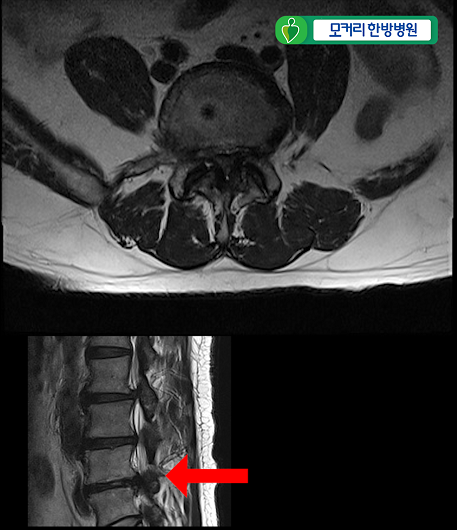

<2-3번>

이 환자분은 협착증을 25년간 앓으시고 증상도 매우 심하신 환자분입니다.

허리 세 마디 2번 3번, 3번 4번, 4번 5번, 이렇게 세 마디의 척추관이 심하게 막혀 있습니다.